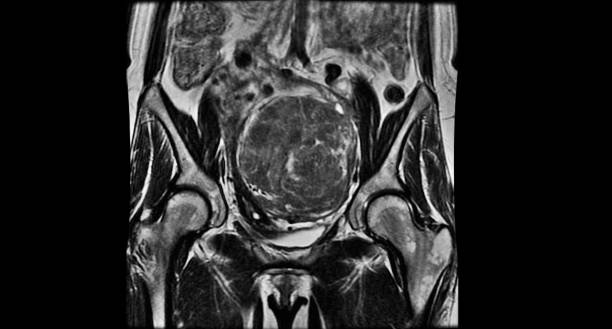

골반 통증 원인 일곱 번째는 자궁내막증 혹은 자궁근종입니다. 여성은 임신과 출산을 위해서 남성 골반과는 구조적으로 다른데 남성 골반보다 넓고 짧아 골반 내 공간이 더 넓은 특징을 가지고 있어 골반 통증에 더욱 취약합니다.

자궁내막증의 경우 생리 혹은 생리 직전에 골반통을 유발하는데 이는 자궁내막조직과 자궁이 아닌 다른 부위의 조직에 부착하여 증식하면서 발생합니다. 자궁근종의 경우 자궁의 평활근에 생기는 종양의 일종으로 별다른 증상이 없을 수 있지만 근종의 위치나 크기에 따라 다양한 증상이 유발되며 이로 인하여 각종 골반통, 생리통, 골반 압박감과 생리량 과다 증상 등이 발생할 수 있습니다.